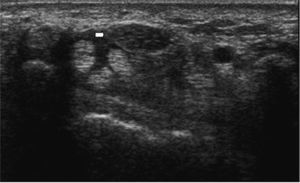

Se realizó EMG de forma estandarizada para registrar los siguientes parámetros: velocidad de conducción sensorial (m/s), latencia motriz distal (ms) y latencia sensitiva distal (ms). Se recogió también la valoración final del neurofisiólogo (normal, leve, leve-moderado y severo). La exploración ecográfica se efectuaba en las 72 horas siguientes a la EMG; se utilizó un equipo General Electric Logic 5 Pro, con sonda lineal de 12MHz. La adquisición de las imágenes fue realizada por 3 reumatólogos, de forma consecutiva, ciega e independiente, uno de ellos experimentado en ecografía osteomuscular, y 2 residentes de reumatología de cuarto año, con nociones básicas de ecografía y un entrenamiento específico de 6 horas. Se archivaban imágenes de todos los cortes representativos. Se pidió a los pacientes no comentar su sintomatología durante la exploración. Ésta se efectuaba con el paciente sentado de cara al ecografista, con el antebrazo sobre una mesa con la palma de la mano hacia arriba. Se exploraba el nervio mediano en todo el recorrido del túnel carpiano de forma transversal y longitudinal. Se obtuvieron imágenes en tres áreas topográficas: a la altura de la articulación radiocubital, a la altura del hueso grande y distal a él (niveles proximal, medial y distal respectivamente). En cada una de estas regiones se medía: el AST, que se calcula con marcadores digitales trazando el margen en torno al nervio internamente al perineurio; el índice de tumefacción (AST medial/AST distal); el desplazamiento palmar, medido como la distancia entre una línea que une el borde superior del trapecio y del ganchoso y el ápex del retináculo flexor, y los ejes transversos mayor y menor.

De entre las localizaciones estudiadas, la que rinde mayor sensibilidad para una misma especificidad es el área distal y, en segundo lugar, el área máxima de las tres consideradas. El mejor punto de corte establecido a través de la curva ROC fue 9,5mm2 de área distal, que clasifica correctamente al 81% de los pacientes.